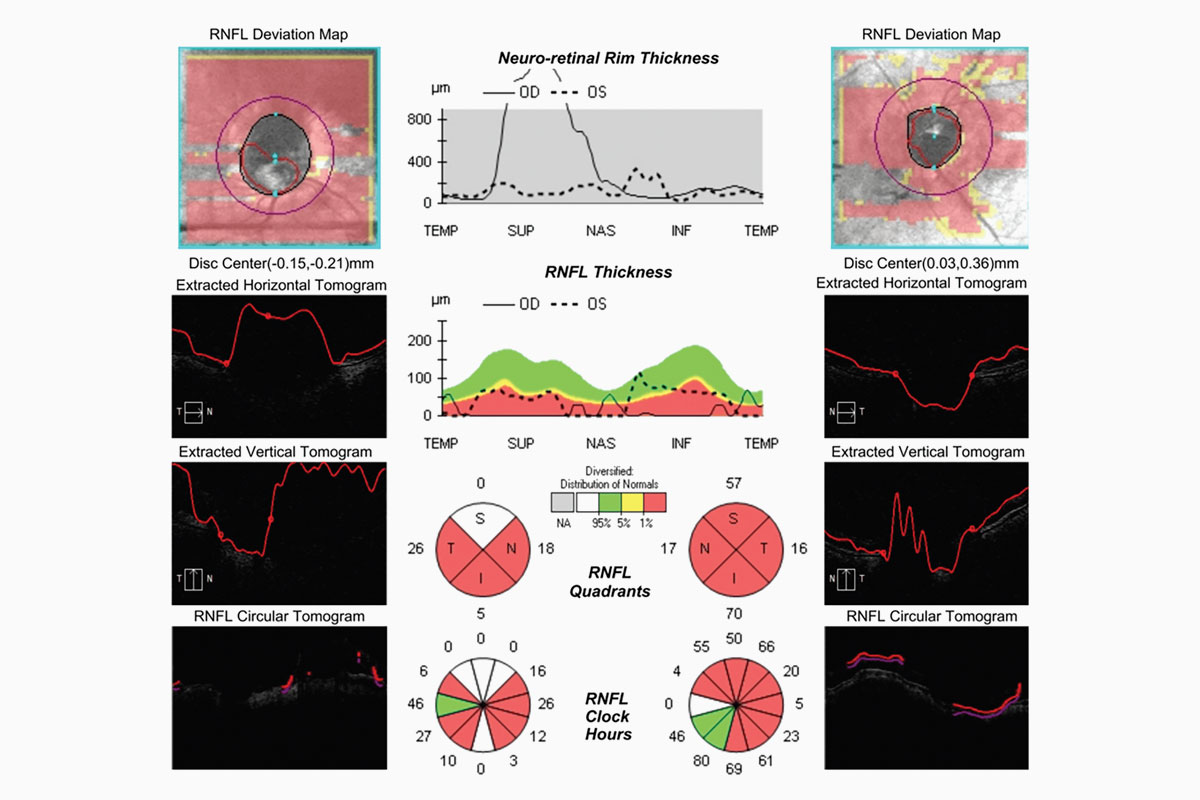

Si bien son lentes que tienen las mismas indicaciones de un LIO monofocal, hay que evaluar la indicación en pacientes con otras patologías como glaucoma, alteraciones maculares, operados previamente de cirugía refractiva, etc., ya que sin duda aparecen como una buena opción para estos casos, pero no hay muchos estudios realizados aún.